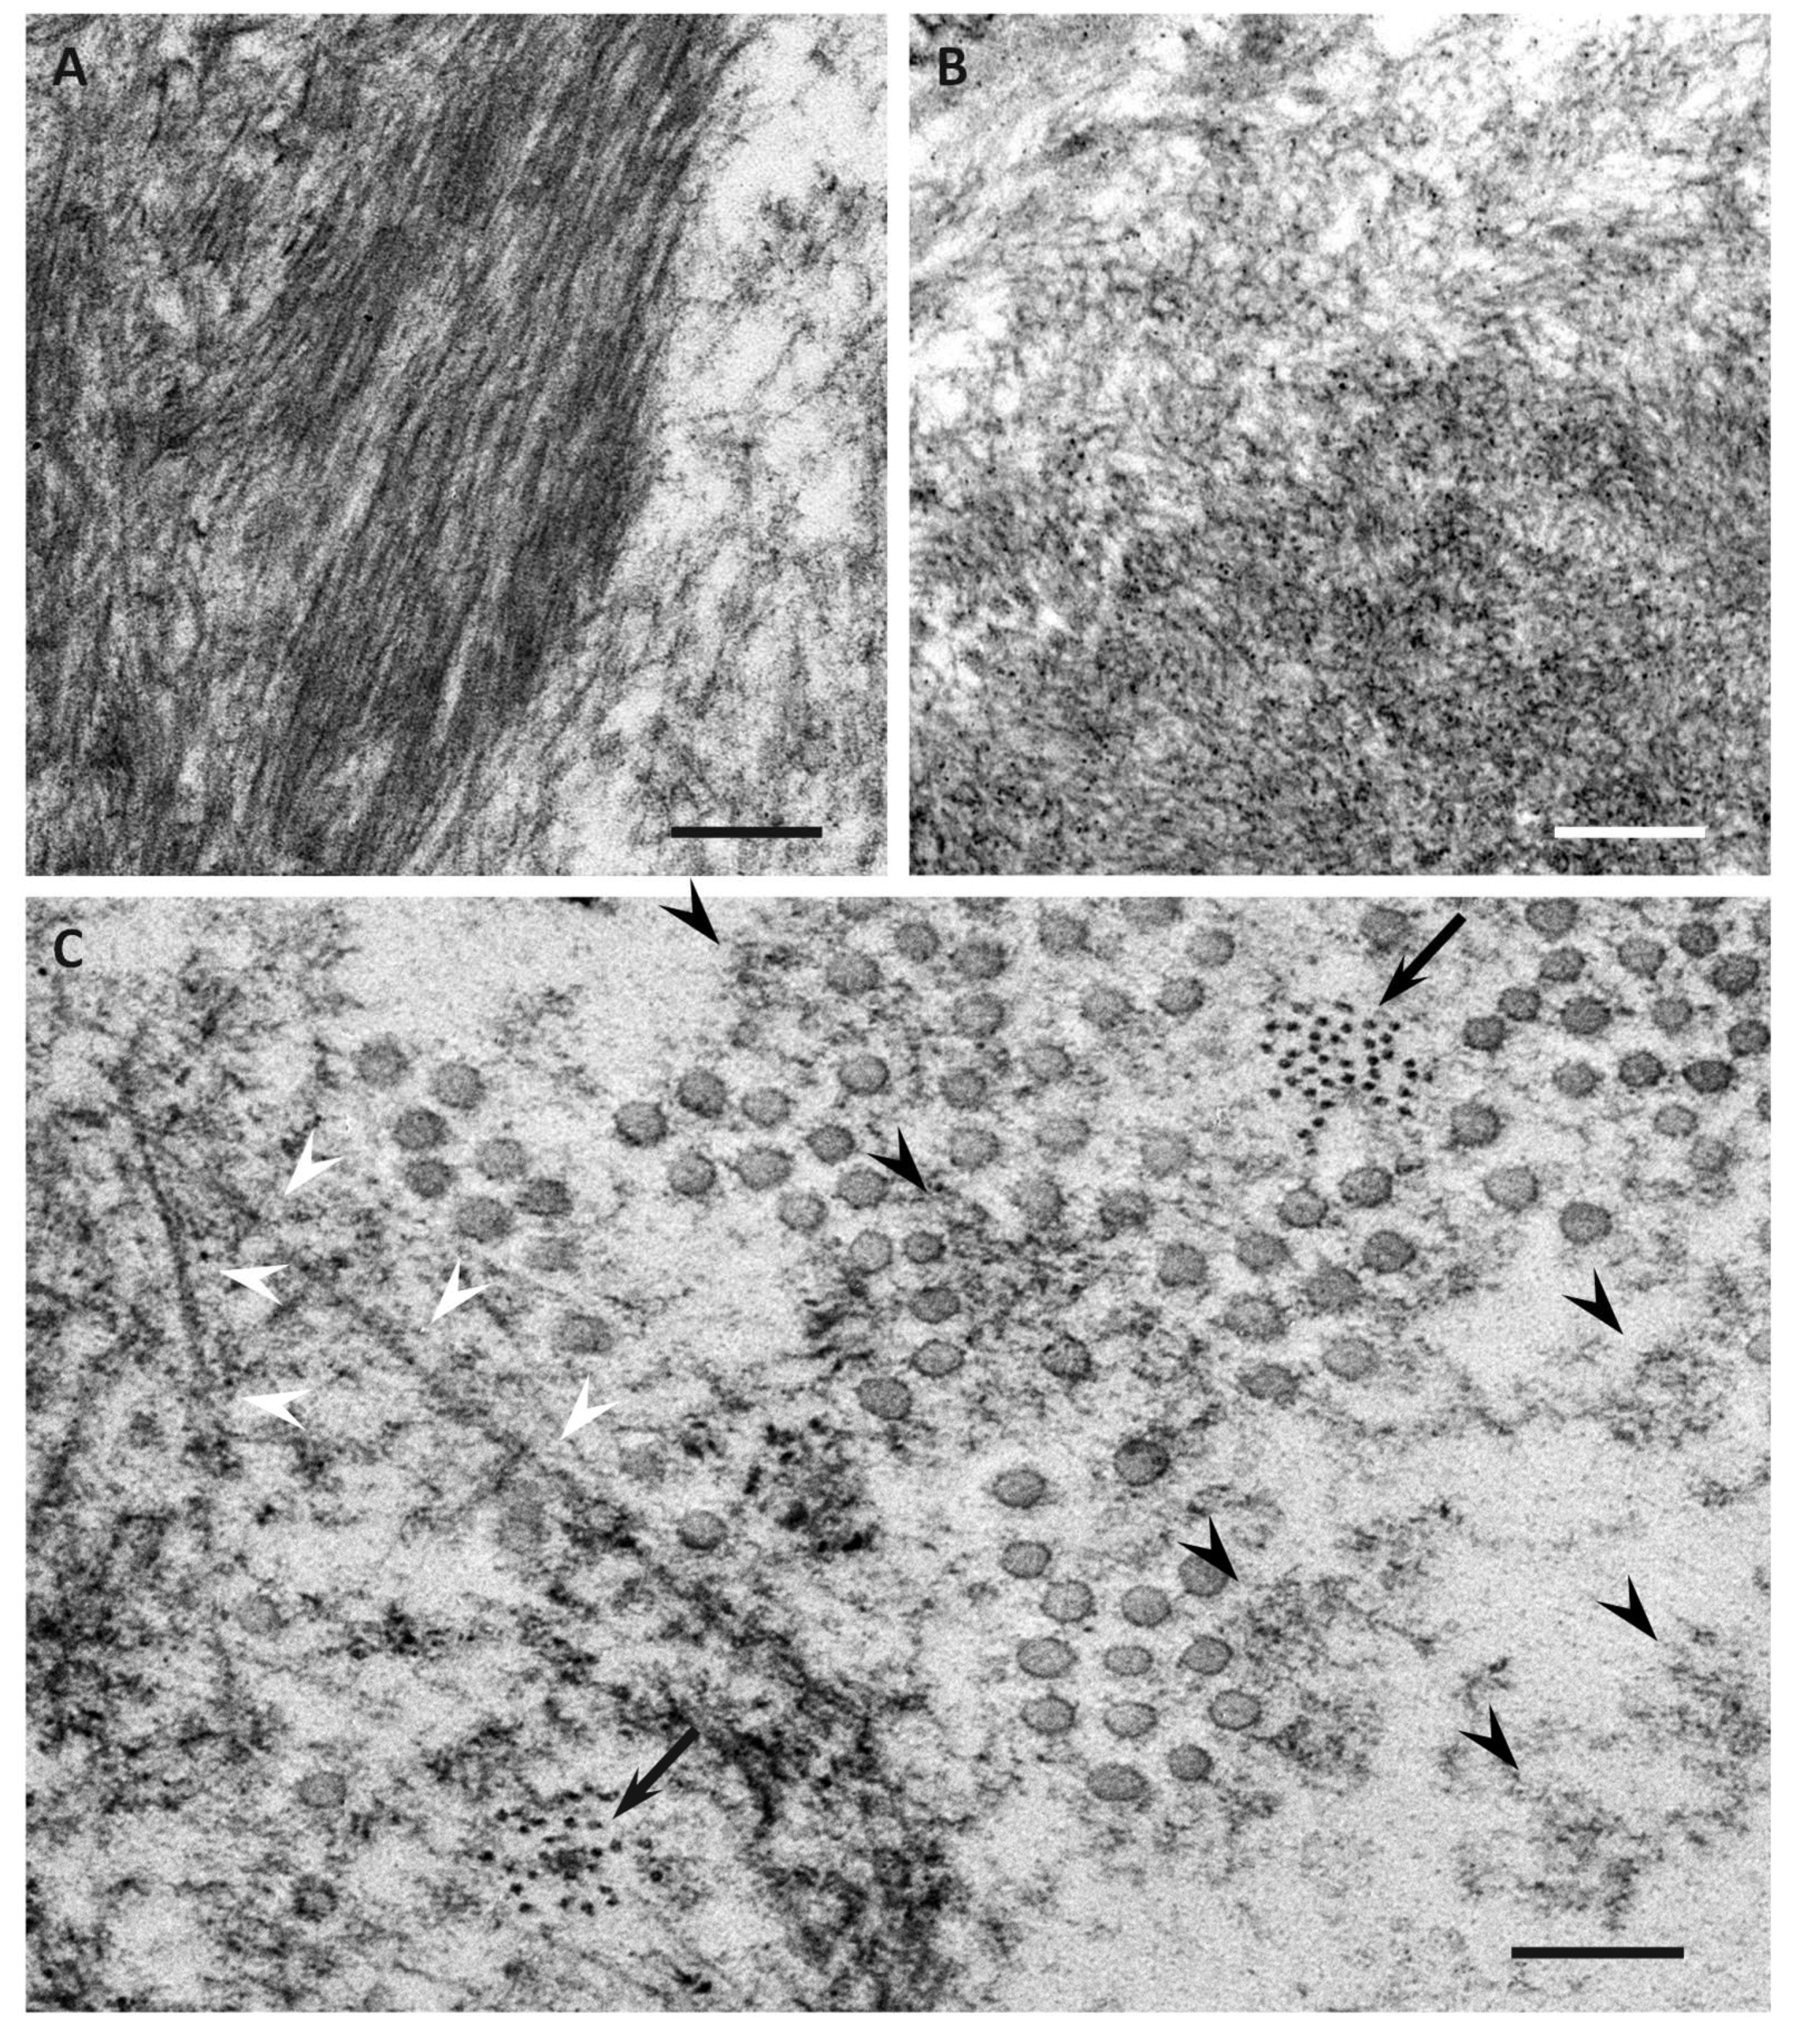

Amyloidosis is caused by the aggregation of insoluble fibrous deposits of misfolded proteins.

Cardiac amyloid deposition, causing an infiltrative/restrictive cardiomyopathy, is a frequent feature of amyloidosis10. Alternative for invasive renal or cardiac bx? Cardiac amyloidosis is an increasingly contributor of degenerative cardiac diseases. These deposits make it hard for the heart to there are many forms of amyloidosis. Signs and symptoms may include diarrhea. Amyloidosis is caused by the aggregation of insoluble fibrous deposits of misfolded proteins. Updates in diagnosis and management. Cambodia cameroon cape verde cayman islands central african republic chad chile china christmas island cocos (keeling) islands colombia comoros congo congo, the.

Cardiac amyloid deposition, causing an infiltrative/restrictive cardiomyopathy, is a frequent feature of amyloidosis10.